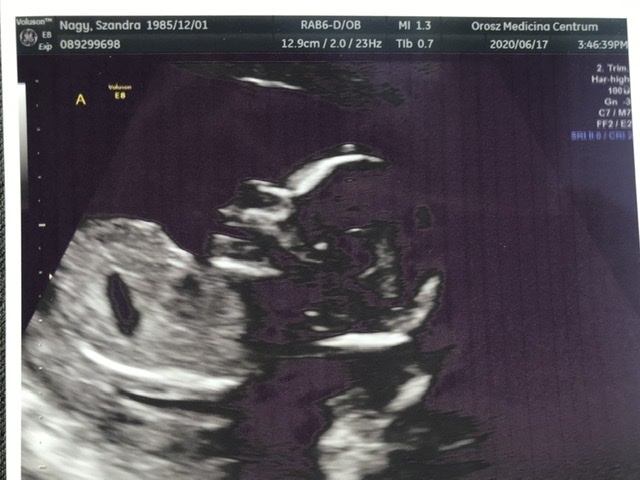

Én hétfőn voltam 12 hetes UH-n 13 hetesen

Szívhang, orrcsont, tarkóredő 1,4 mm, ülőmagassága 63mm. Azt mondta a doki minden rendben,megfelelően fejlődik. Sajnos a férjem nem jöhetett be (nálunk Erdélyben még komoly megszorítások vannak sajnos), viszont a doki adott néhány fotót 3Dt is, hogy mutassam meg a leendő apának. Nagyon cuki volt. A nemét is megtudtuk, 90 százalékban kisfiú a doki szerint, nem volt túl szégyenlős a babóca